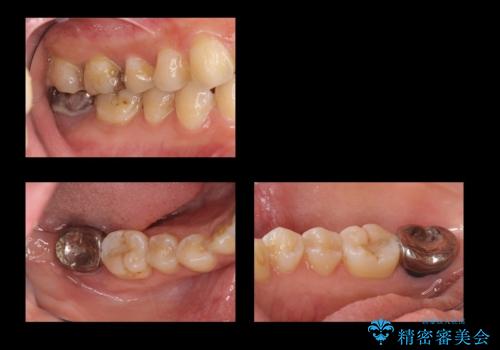

![[ 臼歯部インプラント治療 ]ボロボロになった歯を治療したいの症例 治療前](https://seimitsushinbi.jp/wp/wp-content/uploads/2022/05/9a03b3d2829719a5941e0da7ab0008ec-500x350.jpg?v=1653278074)